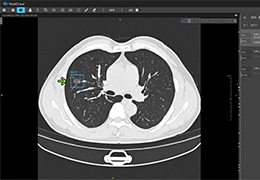

ART-Plan™ Artificial Intelligence Contouring